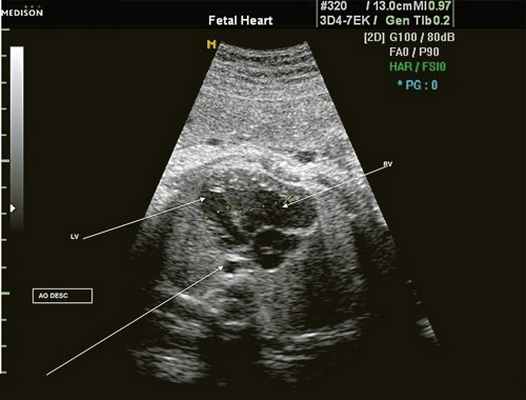

Рис. 3. Трехмерное изображение сердца и аорты плода в 16 нед беременности. Стрелкой указано место сужения аорты. AO DESC - нисходящий отдел аорты, COR - сердце.

Рис. 4. Диспропорция размеров желудочков сердца при коарктации аорты. RV - правый желудочек; LV - левый желудочек; AO DESC - поперечное сечение нисходящего отдела аорты.